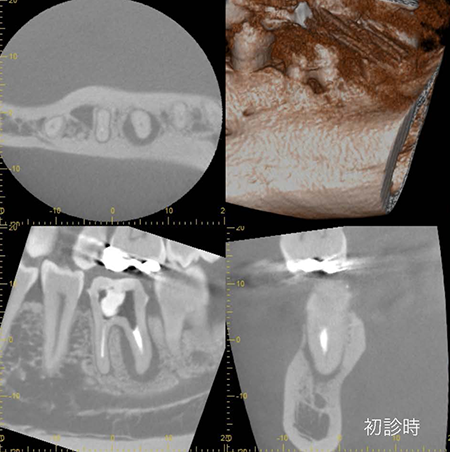

他院で数年前に根管治療を行っていますが、レントゲンから根の周りに透過像(骨吸収)が見受けられます。

術前に診査診断を行った上で、患者様に説明をし顕微鏡での根管治療を選択されました。

今回のケースは細菌の取り残しによって症状を引き起こしています。顕微鏡で精密な根管治療を行なったことにより8ヶ月後のCT像から透過像(骨吸収)が消失し、骨が完全に再生しています。適切な処置を行えば、歯を保存することができます。